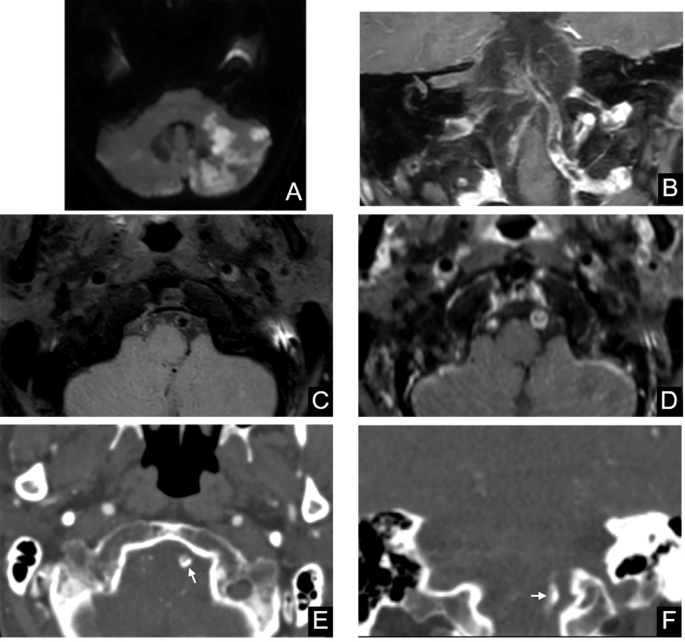

Representative case of a 67-year-old male patient presenting with hemodynamic impairment infarction. Diffusion-weighted imaging (A) demonstrated territory infarcts of the left cerebellum. Post-contrast vessel wall MRI in coronal view (B) revealed diffuse wall thickening in the V4 segment of the left vertebral artery. Pre-contrast (C) and post-contrast (D) vessel wall MRI images showed the presence of a plaque in the left vertebral artery (arrow). Axial (E) and coronal (F) CT images demonstrated the presence of IEL predominant calcification (arrow) in the corresponding image slices.